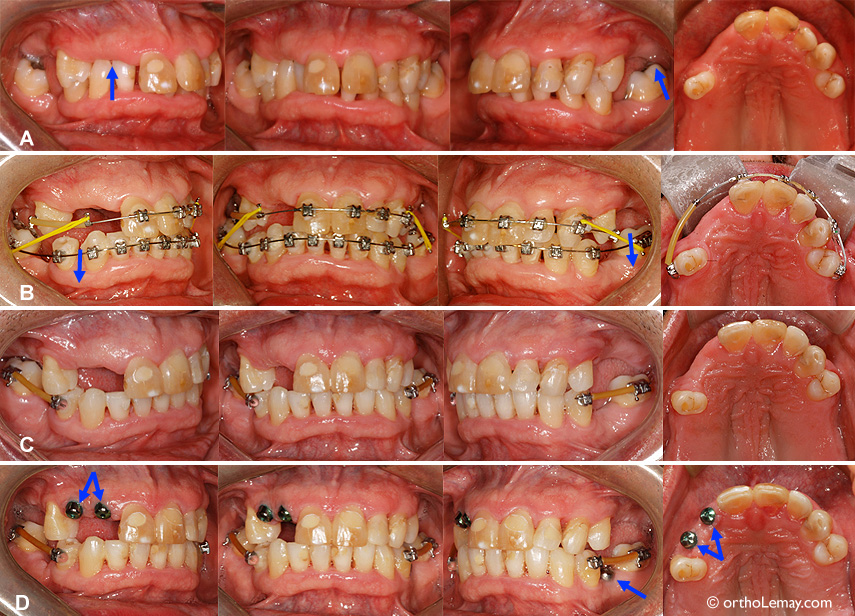

(A) Malocclusion avec occlusion croisée antérieure et usure importante sur certaines incisives.

(B) À la fin des corrections orthodontiques; les dents antérieures sont dans une position plus fonctionnelles qui minimisera les chances d’usure à long terme. La mandibule est reculée en relation normale par rapport au haut. Les espaces édentés seront comblés par des couronnes sur implants. Les flèches indiquent les implants qui sont prêts à recevoir les couronnes.

(C) Après restauration des incisives usées par le dentiste à l’aide de facettes.